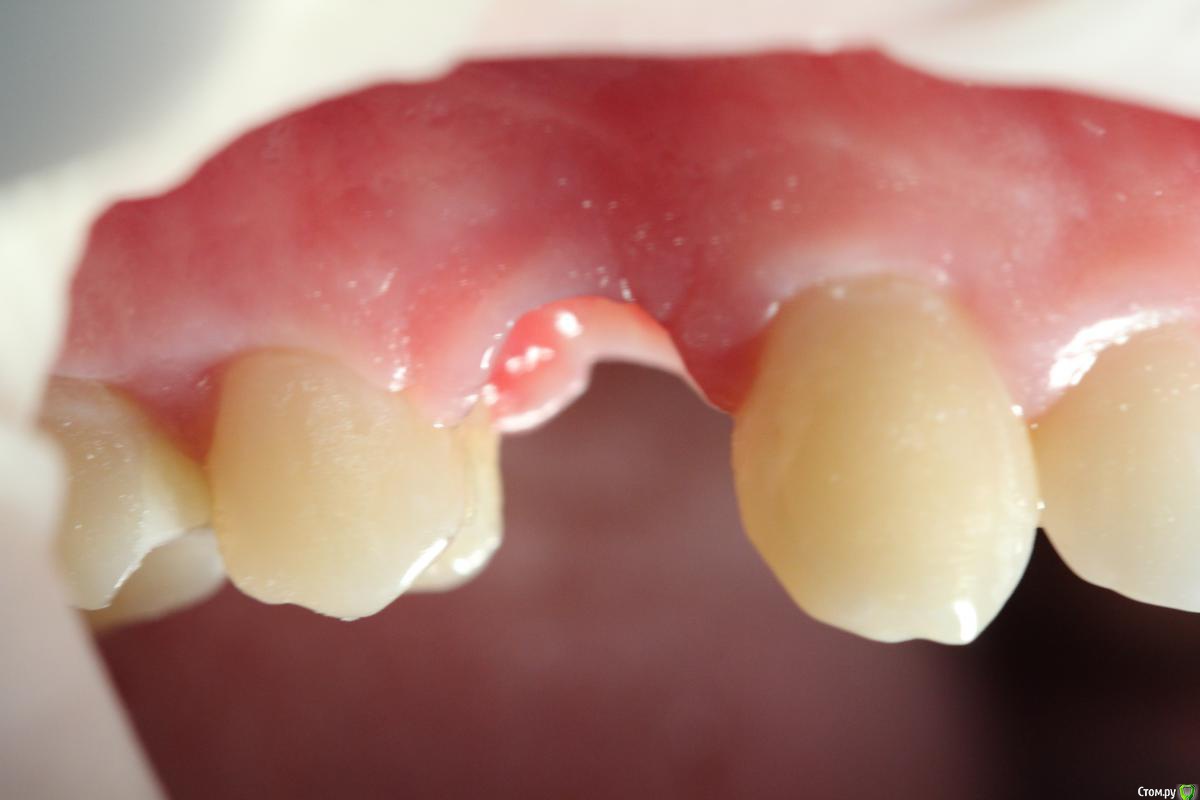

Популярный пост Mane Опубликовано 8 февраля, 2015 Популярный пост Поделиться Опубликовано 8 февраля, 2015 Зафиксировал в субботу. Собственно удалось размоделировать десну просто временной коронкой с заданным профилем прорезывания. Но для этого необходимо было выполнить ряд условий. Каких, доктора? http://i1218.photobucket.com/albums/dd412/Edikn73/emergence%20profile/Emergenceprofile001_zps040f2603.jpg http://i1218.photobucket.com/albums/dd412/Edikn73/emergence%20profile/Emergenceprofile002_zpsaa7acb0b.jpg http://i1218.photobucket.com/albums/dd412/Edikn73/emergence%20profile/Emergenceprofile003_zps259f0885.jpg http://i1218.photobucket.com/albums/dd412/Edikn73/emergence%20profile/Emergenceprofile004_zps6a15b901.jpg http://i1218.photobucket.com/albums/dd412/Edikn73/emergence%20profile/Emergenceprofile005_zps51a41bc2.jpg http://i1218.photobucket.com/albums/dd412/Edikn73/emergence%20profile/Emergenceprofile006_zps3c83a34d.jpg http://i1218.photobucket.com/albums/dd412/Edikn73/emergence%20profile/Emergenceprofile007_zpsba4d3d78.jpg 26 Ссылка на комментарий

Mane Опубликовано 10 февраля, 2015 Автор Поделиться Опубликовано 10 февраля, 2015 По поводу профиля прорезывание интересен Ваш протокол. Менялся ли ФДМ на более широкий, делались ли насечки на десне во время фиксации времяхи? Во первых - это заглубление платформы импланта - от будущего зенита до платформы - 3,5 мм . если этого не сделать - ничего не полуитсяпосле тонкого фдм зафиксировал временную коронку с небольшим надрезом по контактам. отдыхала с времянкой 1,5 мес.далее вы видели 1 Ссылка на комментарий

Евгений Ходыкин Опубликовано 10 февраля, 2015 Поделиться Опубликовано 10 февраля, 2015 Что значит "надрез по контактам" это как?Это когда у вас манжета десневая достаточно высокая от платформы имплантата, чтобы не создавать лишней ишемии при установке временной коронки, да и банально чтобы села, делаются послабляющие разрезы. На н.ч. апроксимально. 3 Ссылка на комментарий